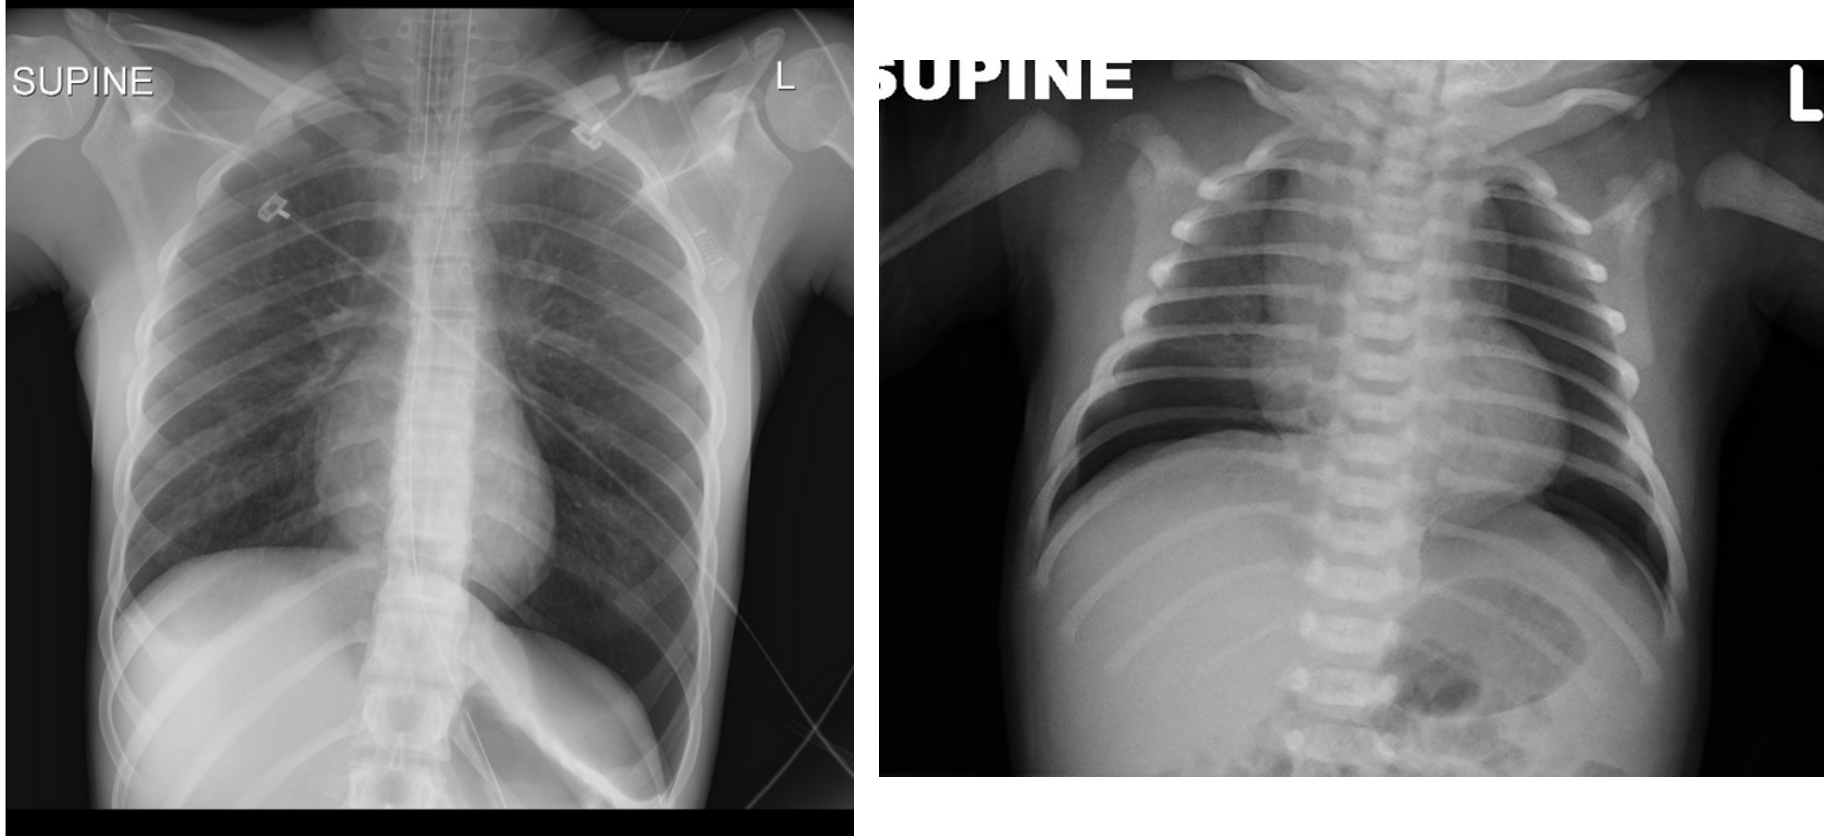

The infant has been on a ventilator for about 6 hours when you are called to the bedside for sudden decompensation with decreased saturations as low as 30%, bradycardia, and absent breath sounds on the right.

- What do you expect happened? pneumothorax

- What is your immediate action? right needle decompression 2nd intercostal mid clavical

well demarcated right lung pnumothorax - pushed

if light goes throughout lung theres pneumothoraxm if localized, its not pneumothorax.

High-intensity fiber optic light demonstrating increased transillumination on the left half of the chest suggestive of left-side pneumothorax compared to the normal right chest.

Deep Sulcus Line

- Notice:

“Deep sulcus line” indicating pneumothorax.

Continuous Diaphragm Sign

- Description:

The blue arrow points to the “continuous diaphragm sign.” The entire diaphragm is visualized from one side to the other because air in the mediastinum outlines the central portion, which is usually obscured by the heart and mediastinal soft tissue structures that are in contact with the diaphragm. The red arrow points to the air beneath and posterior to the heart. Pneumomediastinum elevating the thymus causing the “spinnaker sail” sign. Notice also the “continuous diaphragm line.”